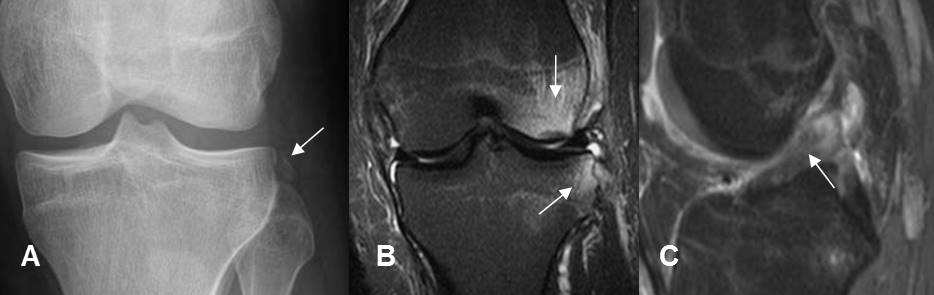

Fig 205. Fractura de Segond.

A: Rx AP de rodilla. Fragmento óseo por encima de la cabeza del peroné, paralelo al borde del platillo tibial, que corresponde a fractura de Segond.

B: RM coronal en STIR. Contusión asociada del cóndilo femoral y platillo tibial lateral.

C: RM sagital en STIR. Este tipo de lesión se asocia con ruptura del LCA.